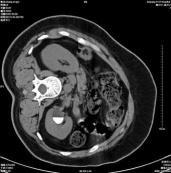

• 腎鈣乳

628健康網為您分享有關腎鈣乳的癥狀,腎鈣乳的治療方法,腎鈣乳的預防知識,腎鈣乳的癥狀圖片,腎鈣乳吃什么藥,腎鈣乳怎么治...